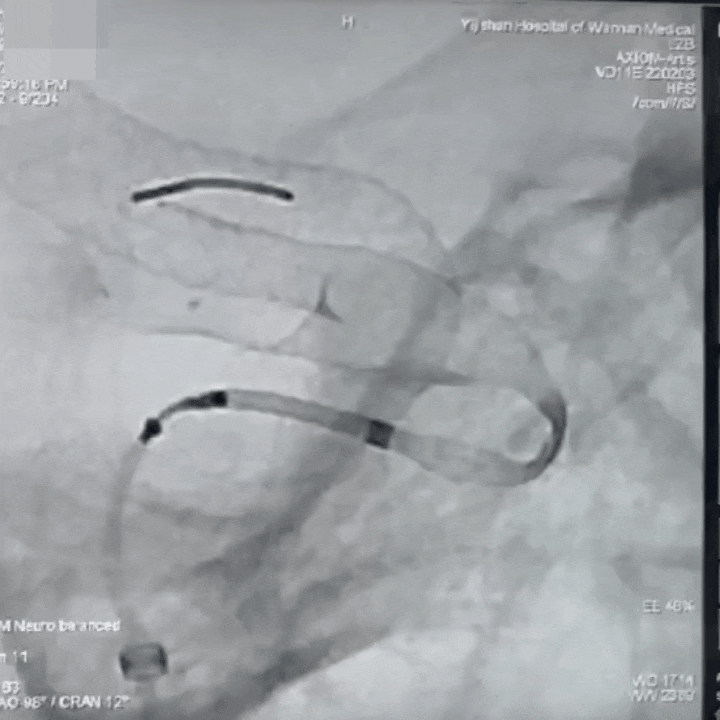

通桥麒麟™血流导向密网支架成功释放。

通桥麒麟™血流导向密网支架完全释放,术后造影。

术后血管造影见动脉瘤仍有显影,瘤腔内造影剂滞留,支架展开,贴壁良好,载瘤血管血流通畅,手术顺利。